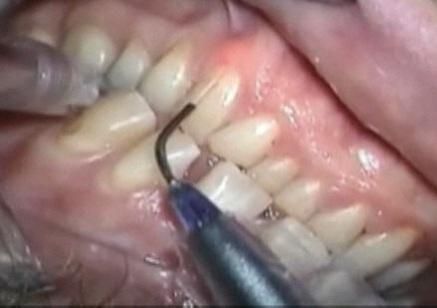

- Parodontologia

- Mucositi-perimplantiti